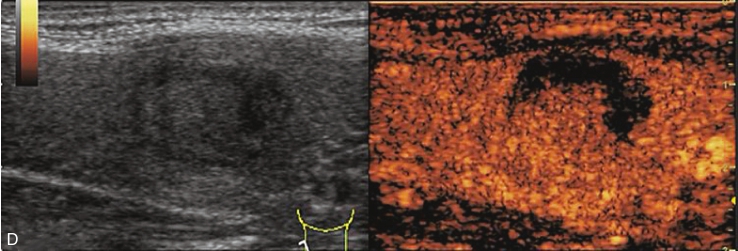

甲状腺左叶下极结节超声造影全程呈整体无增强,病灶边界清楚,无增强面积等于灰阶超声所示,见图1-3-6、ER1-3-3。

(1)病灶增强的边界清楚。

(2)一般为圆形或者椭圆形。

(3)病灶为整体无增强。

(4)无增强范围等于灰阶超声所示。

图1-3-6 超声造影声像图

ER1-3-3 甲状腺囊肿伴出血超声造影视频